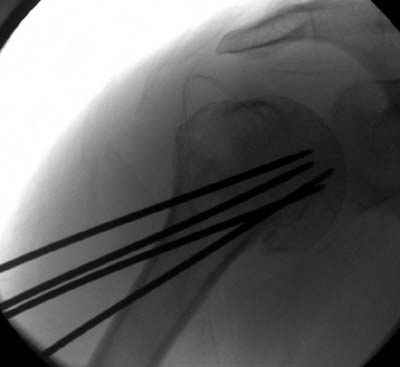

Здесь случай перелома-вывиха плеча, больному 56 лет, после "дважды" закрытой неудачной репозиции, опять же ургентно взяли в операционную, после полного общего обезболивания попытались сделать репозицию, и фиксацию провели спицами.

Больной находился в повязке, примерно напоминяющей косыночную, рекомендованы движения в локтевом суставе и маятниковые движения в плече, спицы удалены в три недели (были случаи миграции)

Сегодня взял больного повторно в операционную, не скажу, что повторная репозиция через неделю после первой попытки, была простая.

После удаления спиц попытался манипулировать отломками, но безуспешно, поэтому пришлось пользоваться периостальным элеватором, чтобы устранить смещение отломков и перепровести спицы. Проверил и перепроверил стабильность фиксации под ЭОПом, завтра Рг- будет готов, вот и поглядим....

Да. У нас довольно скромный опыт такого остеосинтеза (по 2 случая - плечо и наружная лодыжка), дошли до использования самого простецкого троакара, через который мы сверлим кость и вводим 6 мм стержни, когда накладываем аппарат. Соответственно, в качестве забойника отлично работает любой стержень от аппарата Илизарова. Еще из наших туземных особенностей - страшная любовь к спицевым дистракторам, поэтому делали в нем. Результат у этой дамы неизвестен, т.к. она из области и уехала рожать сразу после остеосинтеза, сейчас прошло больше 5 месяцев...

Что-то, наверно, сделали мы не совсем оптимально, поскольку у Анатолия Федровича и его соратников как-то красивее "раскрываются" спицы в головке плеча - надеюсь, он прокомментирует и подскажет, что надо подправить.